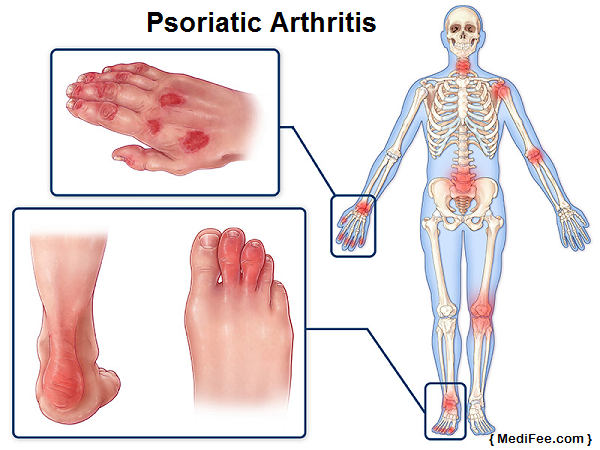

Psoriatic Arthritis:

People suffering from psoriasis are more likely to develop psoriatic arthritis. Psoriasis is a skin disease that results in red, itch and patchy skin. This is also a type of autoimmune arthritis similar to rheumatoid.

Anyone between age group 15 to 35 years may develop this condition. Psoriatic arthritis affects different joints – small or large. Depending on the location where it is experienced, psoriatic arthritis is of various types. Spondylitis is one of the most common forms of psoriatic arthritis.

Causes:

- Skin infection or excessive scratching

- Bad sunburn may cause psoriasis, that may eventually lead to psoriatic arthritis

- Several drugs, such as those used to treat malaria, and heart disorders etc.

- Emotional stress and anxiety aggravates psoriasis

- Smoking and alcohol consumption

- Puberty and Menopause affect hormonal levels and thus psoriasis, leading to arthritis

- Certain fungal and bacterial infection

Symptoms:

- Typical symptoms fluctuate as they sometimes appear to improve and disappear only to re-appear within a short duration

- Swelling that may lead to deformities of fingers and toes

- Severe pain experienced on lower back

- Pain on the sole of your feet

- Pain and stiffness around the joints

- Conjunctivitis

- Nail Pitting

- Hindered movement